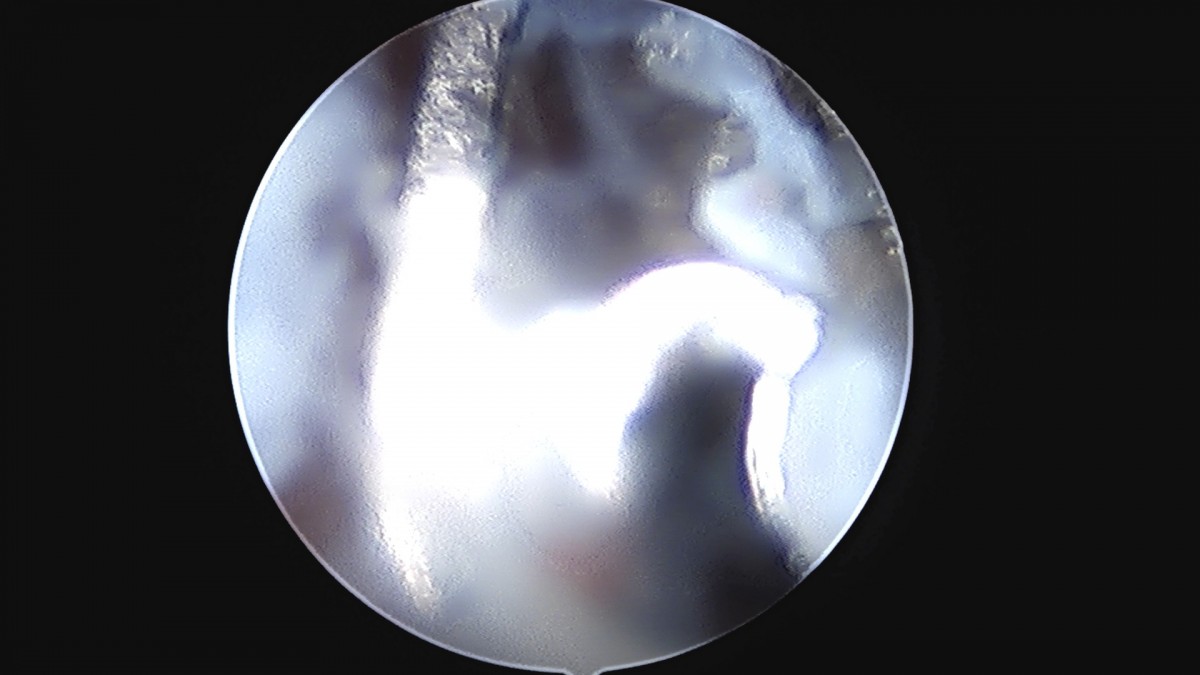

정지영원장님 손목 삼각섬유연골 복합체 봉합술 박현O 환자

작성자 최고관리자 댓글 0건 조회 778회 작성일 25-09-16 16:50